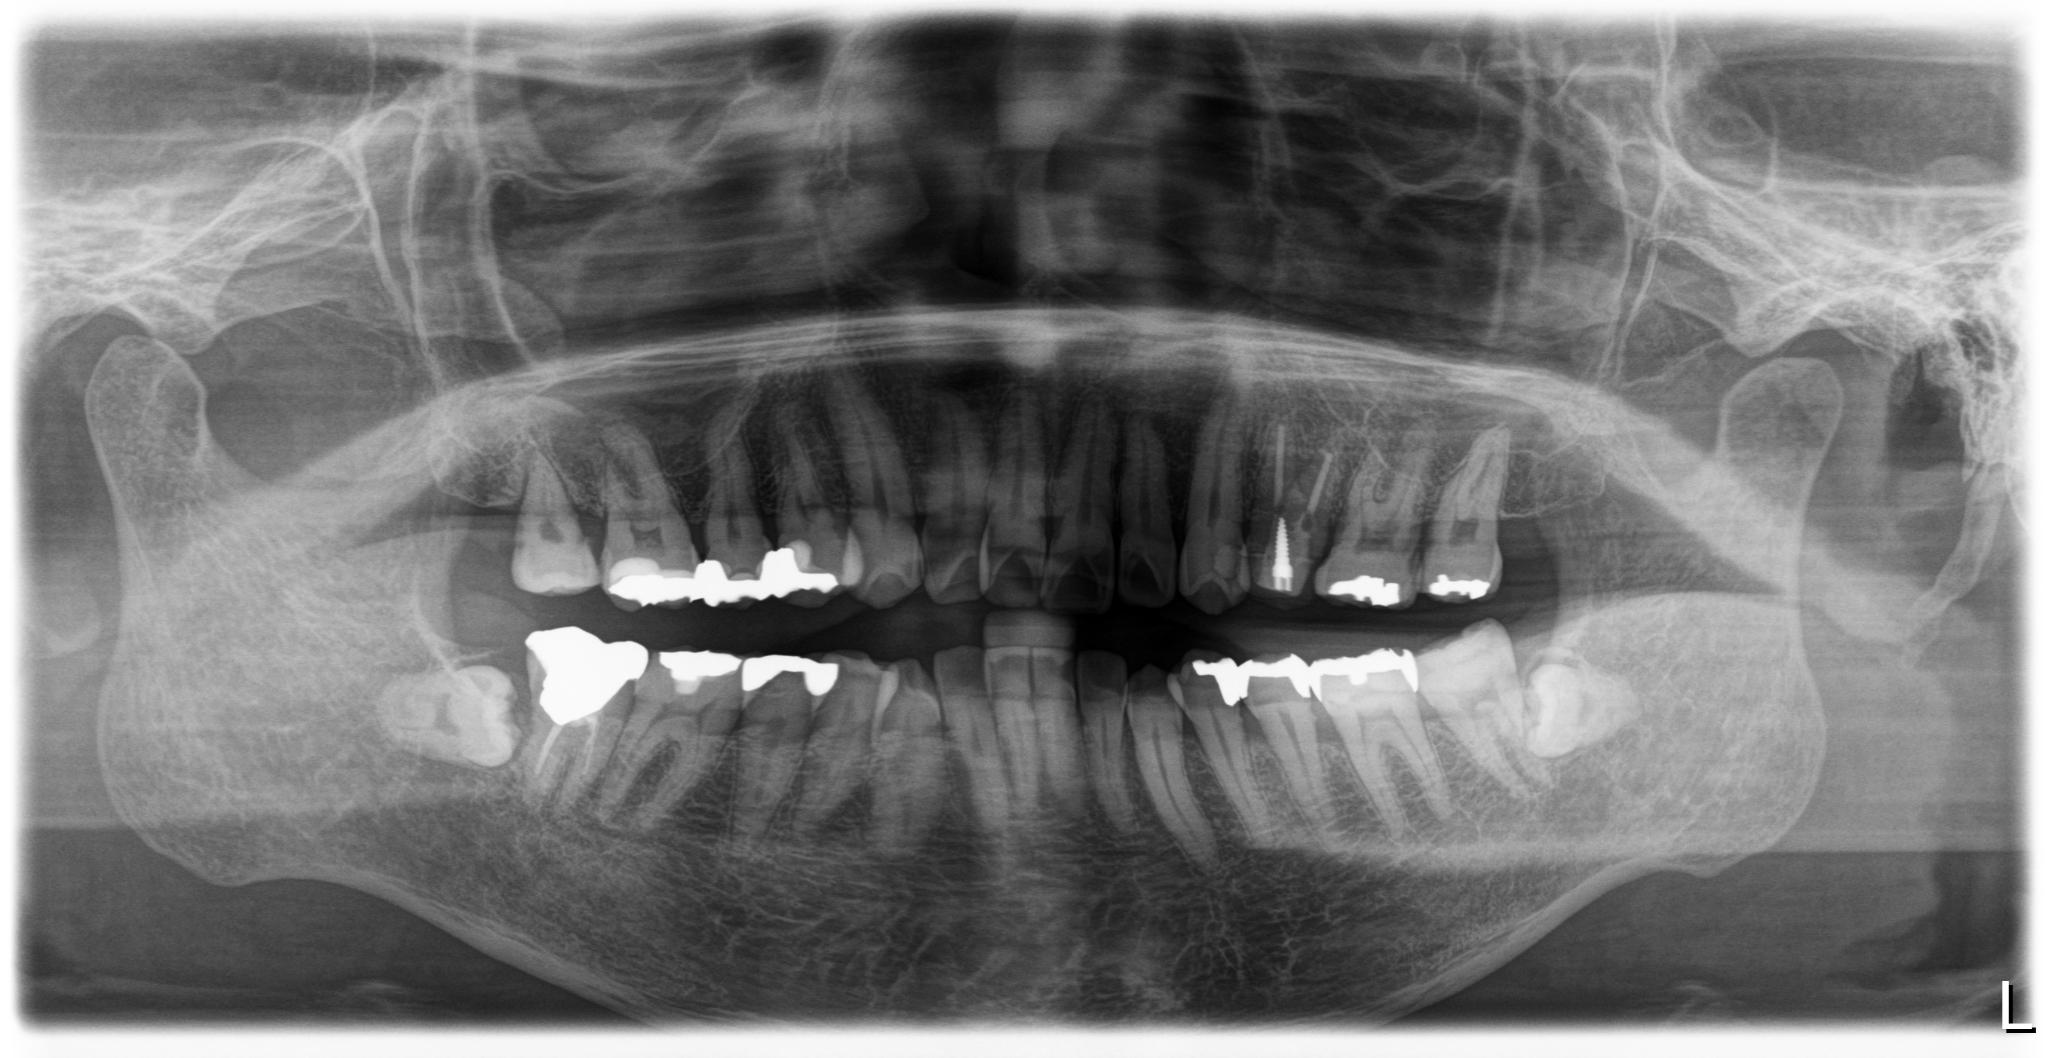

治療前レントゲン画像

治療後レントゲン画像